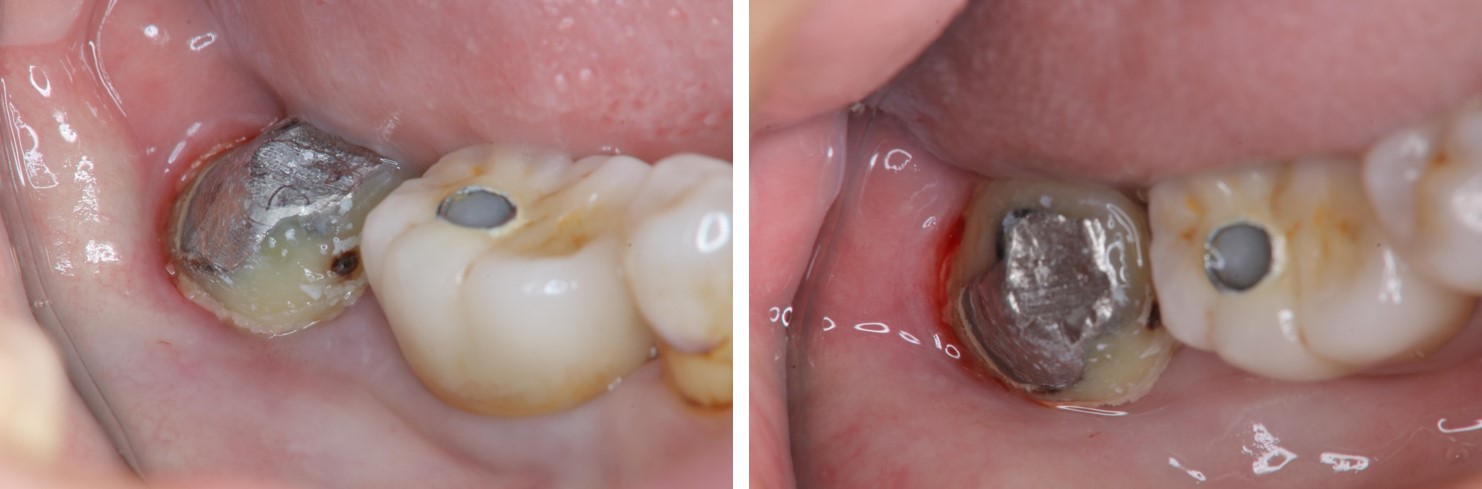

治療前,右下第三大臼齒冷熱敏感

治療前,蛀牙已侵犯至牙髓

鑄造金屬釘柱

水雷射牙冠增長手術

膺復前評估牙齦、牙齒狀態